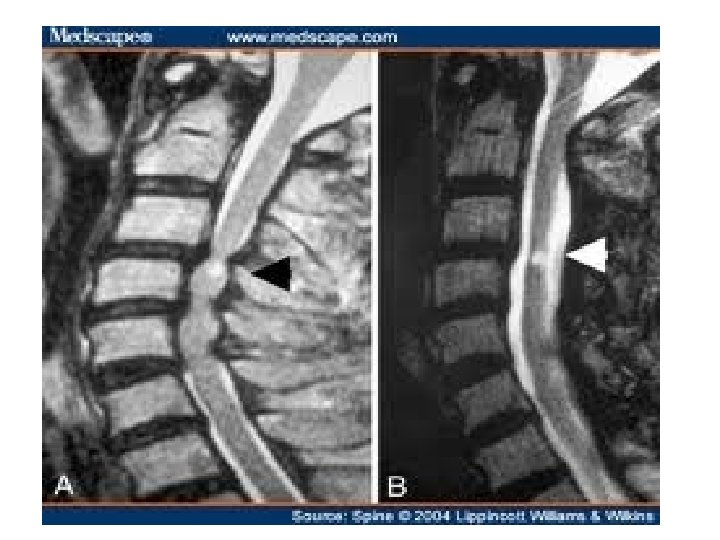

MRI CERVICAL SPINE